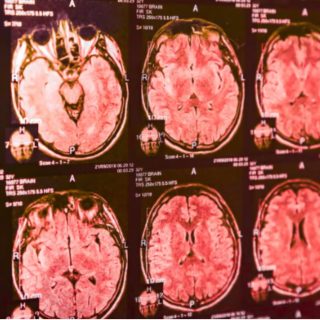

This insight could eventually help doctors diagnose Parkinson’s earlier. Today, identifying the disease often takes years and usually involves a long series of clinical evaluations. A simple smell based test could offer a faster, cheaper and non invasive alternative. Loss of the sense of smell is already known to be…